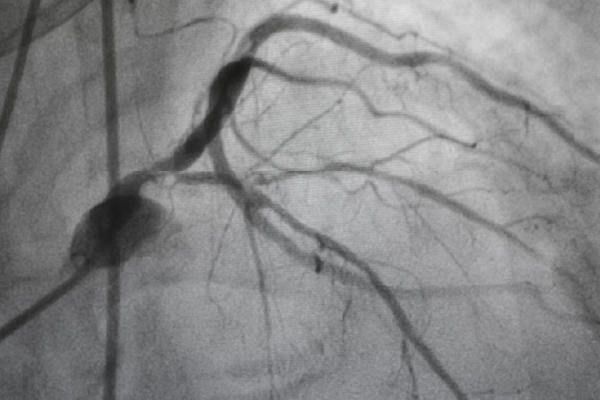

A coronary angiography procedure captures crisp, detailed, and accurate images of blood vessels and blood flow, enabling precise diagnosis and offering efficient treatment opportunities for vascular system conditions. It allows us to provide prompt results that enhance well-curated preventive cardiology services. Having performed the highest number of cardiac procedures with high success rates, we at Yashoda Hospitals provide advanced electrophysiological services that involve various diagnostic procedures and cath-lab technologies to prevent heart conditions. Our comprehensive approach to heart failure management includes advanced therapies such as implantable cardiac devices and structural heart interventions like TAVI and MitraClip.